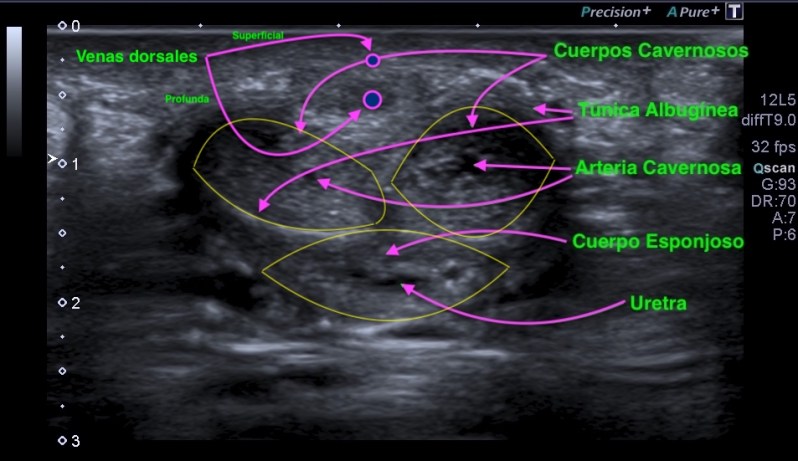

Lo primero que tenemos que conocer es la anatomía ecográfica del pene, el corte axial es normalmente el que mejor visión global del mismo no va a mostrar, ya que vamos a poder ver toda su anatomía y la relación de las diferente estructuras que la componen. Si el abordaje del pene es ventral o dorsal, nos dará una anatomía axial donde la uretra se situará superficial o profunda a los cuerpos cavernosos.

Es muy importante el conocimiento de estas estructuras que tienes señaladas con flechas rosas y líneas amarillas, así como las dos venas superficiales, superficial y profunda dorsales del pene, con lo cual, el acceso al pene ha sido dorsal.

Nos tenemos que fijar en la túnica albugínea de los cuerpos cavernosos del pene, pero ¿qué es? y ¿qué función tiene dicha túnica? Te lo explico..La túnica albugínea es una envoltura de los cuero cavernosos del pene. Básicamente es Colágeno a un 95% y Elastina a un 5% ya que está implicada en el mantenimiento de la erección.

Hemos hablado que esta enfermedad afecta a la túnica albugínea del pene, por lo tanto y según la anatomía que ahora conocemos, incide directamente sobre la capacidad de erección del miembro.

También sabemos como es la normalidad ecográfica de la túnica, una lámina fina, hiperecogénica, a veces a penas perceptible que rodea los cuerpos cavernosos. Los cambios que se produzcan sobre esta normalidad serán relativamente fáciles de ver, si se domina la técnica, esto debe queda claro.